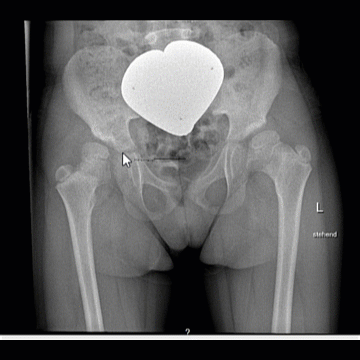

Le module Web Hanche permet de planifier la pose de vos implants de la hanche. Il est basé sur des méthodes courantes de planification des PTH au moyen d’images radiographiques et de modèles de prothèses.

* Avec la dernière version 2.5, la planification automatique de la hanche est également possible avec des fichiers .jpeg ou .png, ce qui permet une plus grande flexibilité dans la sélection des données d’image. *